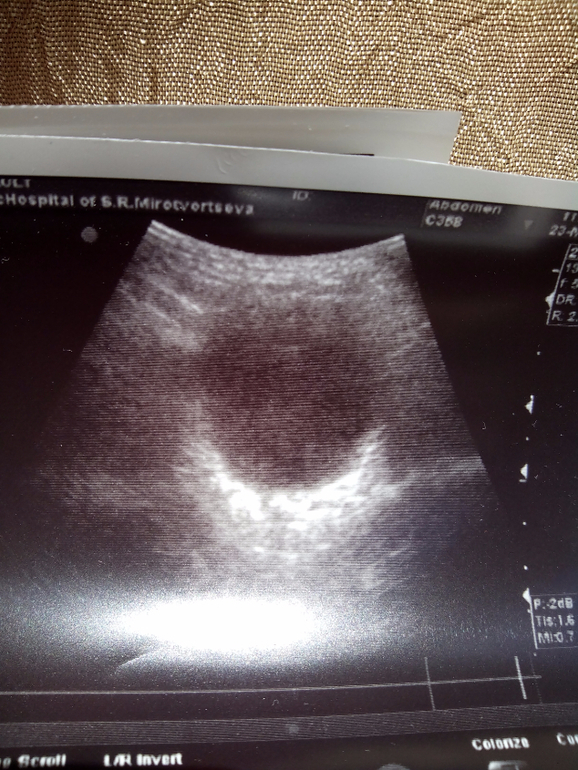

Вот снимки мочевого пузыря. Спасибо за внимание!

мочевой пузырь на момент осмотра 11,4 мм, просвет анэхогенный, мочеточники не виз-ся.

Заключение: эхо-признаки характерные для двусторонней пилоэктазии больше справа, ("наменоза" не разборчиво) справа.